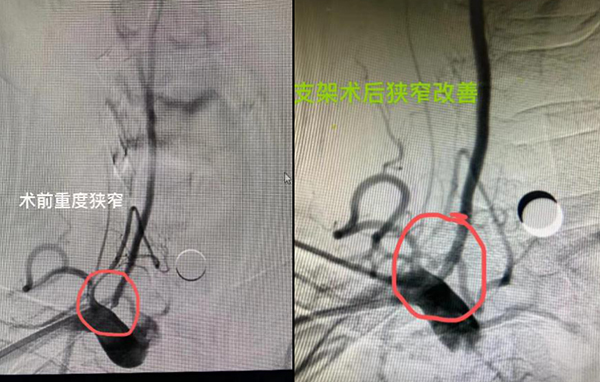

以下是我院一些病例的手术照片:

血管狭窄超过管径的75%时,需做动脉内膜剥脱手术或在狭窄的血管内放置血管支架,以使管腔扩大,达到治疗的目的。

应用较广泛,主要优势在于对患者的创伤小,能同时处理多处狭窄病变,特别适用于手术后血管狭窄又复发、不能耐受或拒绝手术、多支血管狭窄及狭窄部位开放手术无法抵达的患者。